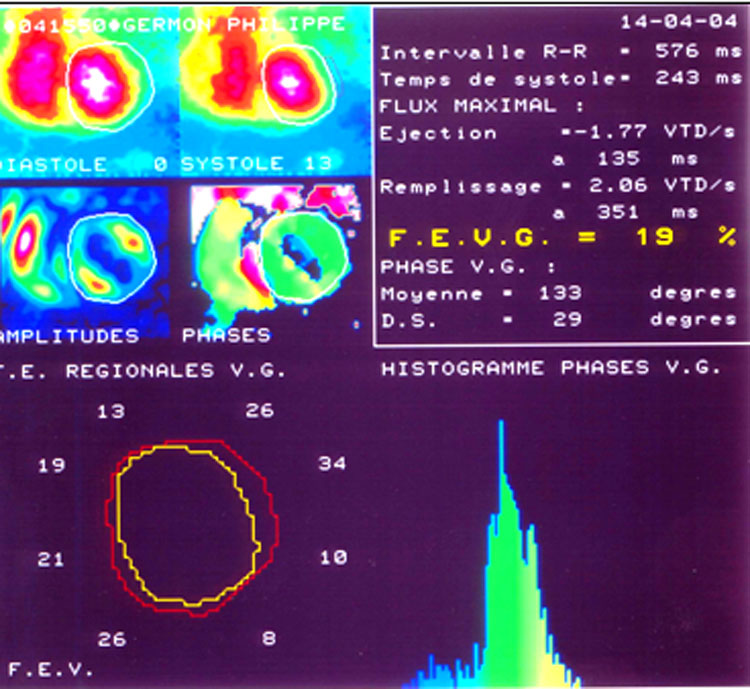

La technique la plus usuelle consiste à enregistrer l’activité des cavités cardiaques en oblique antérieure gauche, en synchronisant l’enregistrement sur l’ECG pour pouvoir déterminer la télésystole et la télédiastole (figure 43).

On peut ainsi mesurer les fractions d’éjection des deux ventricules dont la valeur usuelle normale varie un peu d’un laboratoire à l’autre mais est entre 50% et 70% (la norme du laboratoire est donnée avec le compte rendu). La mesure de fraction d’éjection par cette technique est si fiable et si reproductible lorsque le rythme est sinusal, qu’elle est considérée comme la référence technique pour cette mesure. L’abaissement de la fraction d’éjection globale de repos est un paramètre pronostique très important quelle que soit l’étiologie de la cardiopathie. En simplifiant la littérature, disons que la dégradation de la fonction ventriculaire gauche est patente lorsque la FE du ventricule gauche est inférieure à 50%, avec une détérioration du pronostic qui s’accroît lorsque les chiffres baissent. Lorsque la valeur atteint 20%, le pronostic vital est souvent engagé à quelques mois ou années.

Outre la fraction d’éjection globale du ventricule, on peut étudier des fractions d’éjection segmentaires en découpant la cavité ventriculaire gauche en secteurs. L’abaissement de la fraction d’un ou plusieurs segments contigus ventriculaires, traduit une dysfonction systolique segmentaire. Selon la sévérité de l’anomalie on parle d’hypo-, d’a- ou de dyskinésie de la contraction au niveau de la zone atteinte du ventricule gauche.

Figure 43 : Angiographie isotopique : mesure de la FEVG, ici très abaissée à 19%